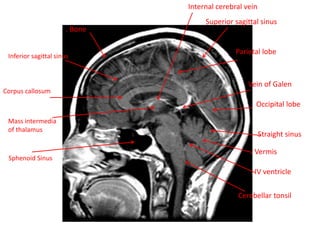

Inferior sagittal sinus

Corpus callosum

Internal cerebral vein

Vein of Galen

Superior sagittal sinus

Parietal lobe

Occipital lobe

Straight sinus

. Vermis

. IV ventricle

Cerebellar tonsil

Mass intermedia

of thalamus

Sphenoid Sinus

. Bone Inferior sagittalsinus Corpus callosum Internal cerebral vein Vein of Galen Superior sagittal sinus Parietal lobe Occipital lobe Straight sinus . Vermis . IV ventricle Cerebellar tonsil Mass intermedia of thalamus Sphenoid Sinus